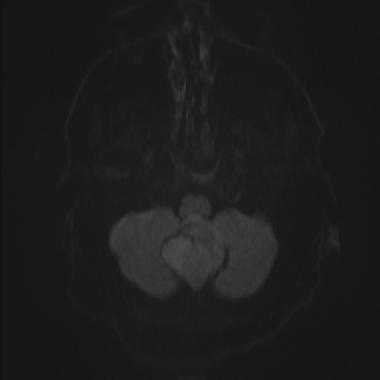

Менингиома задней черепной ямки: диффузионно-взвешенное МР-изображение (DWI). Сигнал умеренно повышен, что соответствует умеренному ограничению диффузии.